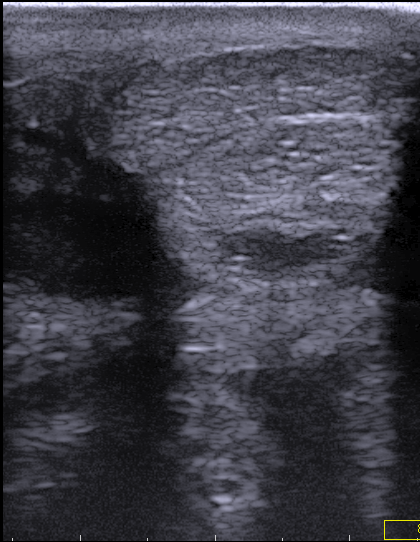

Die Ultraschalluntersuchung (Sonographie) ist das Mittel der Wahl zur Untersuchung von Weichteilgewebe (Muskulatur, Sehnen, Gelenkkapseln, Körperorgane u. a.). Wir setzen die Ultraschalluntersuchung in der Orthopädie, Gynäkologie, Inneren Medizin, bei Augen- und Fohlenerkrankungen ein.

In der Orthopädie ist der Ultraschall in hochauflösender Darstellung ein unverzichtbares Hilfsmittel zur genauen Untersuchung und Quantifizierung von Schäden an Sehnen, Bändern und Gelenken. Die Zyklus- und Trächtigkeitsdiagnostik im Rahmen der Gynäkologie wird durch die Sonographie spezifiziert und optimiert. In der Inneren Medizin kommt zur Untersuchung der Bauchhöhle und Bauchhöhlenorgane (z. B. Darm, Magen, Niere, Blase, Leber) ein Ultraschallgerät mit größerer Eindringtiefe zum Einsatz. Bei der Augenuntersuchung ist die Sonographie ein wichtiges Hilfsmittel zur Beurteilung der hinteren Augenabschnitte. Der Nabel und die Bauchhöhle des Fohlens können gut mittels Sonographie auf krankhafte Veränderungen untersucht werden.